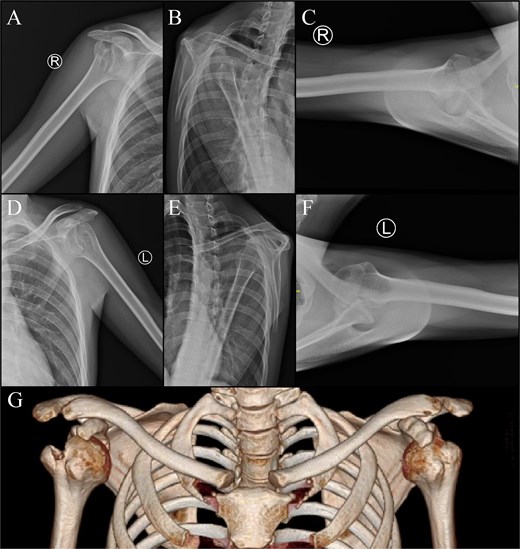

Physical examination was conducted. The deltoid contour was lost on the right and left shoulder. There was no swelling, bruising, wound, or scar found. Neurovascular test on the distal part of both shoulders indicates intact structures. Limitation of shoulder range of motion (ROM) was noted (Fig. 1). Plain radiographs and CT scan (Fig. 2) showed a bilateral anterior dislocation of the glenohumeral joint with GT fracture.

Imaging of the right shoulder : (A) anteroposterior view; (B) scapular Y view; (C) axillary view. Imaging of the left shoulder : (D) anteroposterior view, (E) scapular Y view, (F) axillary view. (G) 3D computed tomography scan.

The patient was then diagnosed with bilateral neglected closed fracture dislocation of proximal humerus Neer 2-part and underwent open reduction with GT osteotomy and PHILOS plate fixation. The right shoulder surgery was performed first, with the left shoulder procedure delayed by three months due to administrative constraints related to public healthcare insurance.